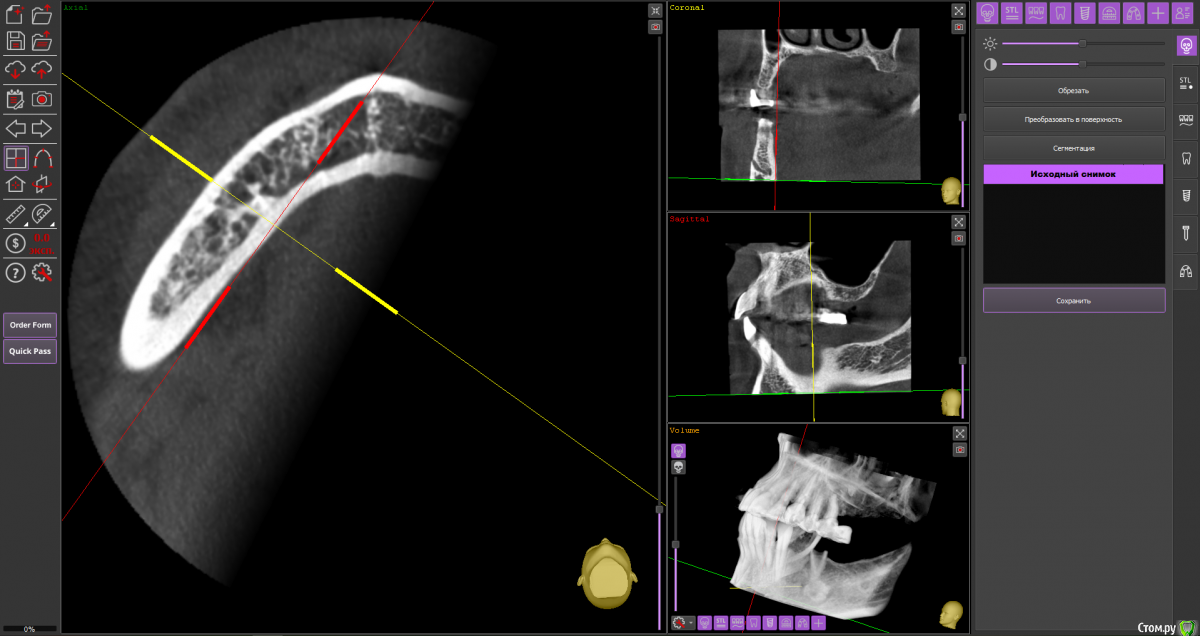

almaz7888 Опубликовано 11 февраля, 2021 Поделиться Опубликовано 11 февраля, 2021 (изменено) Доброе утро коллеги! Подниму тему. Данной пациентке планируется имплантация для замещения концевых дефектов на нижней челюсти. Зуб 3.5 думал удалить во время операции. Образование в области 3.5 это просто склероз кости? В области ментального отверстия справа также имеется какой-то очаг но меньших размеров. Изменено 11 февраля, 2021 пользователем almaz7888 Ссылка на комментарий